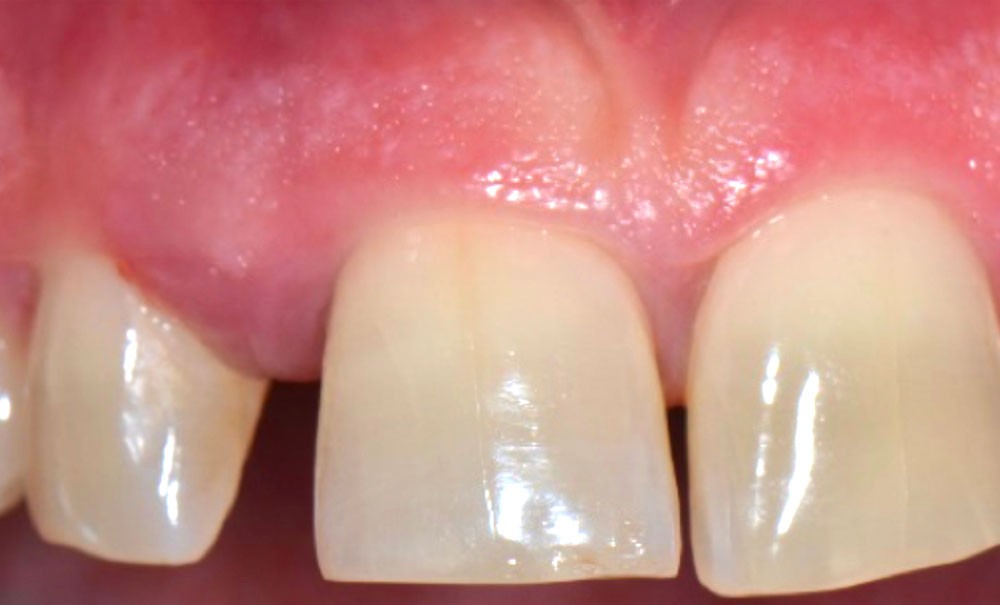

La MDP est une complication fréquente des parodontites et parfois l’un de ses premiers signes cliniques visibles par le patient et son entourage. Sa prévalence est de 30 à 55 % chez les patients atteints de parodontites modérées et sévères [2].

La MDP est dépendante de l’axe des forces appliquées à la dent. Ces forces peuvent ainsi conduire à des déplacements horizontaux, des versions (basculement par rotation) et/ou des égressions/extrusions (déplacement vertical seul, souvent retrouvé lors de la perte de dent antagoniste).

Des combinaisons de mouvements sont le plus souvent retrouvées, notamment lors de la perte du calage postérieur : déplacement horizontal et vertical, migration « en éventail ».